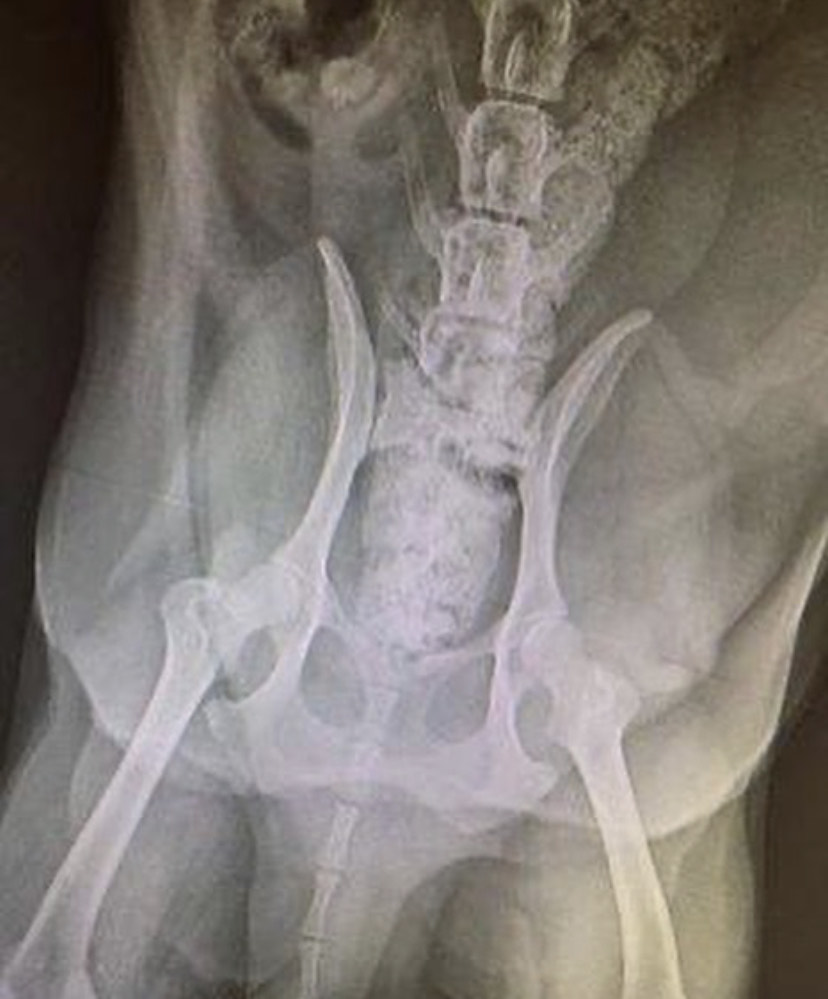

Die Welpen sind nun etwa 2 Wochen alt und öffnen langsam alle nach und nach die Augen! Die Mama wurde vermutlich angefahren und hat aller Warscheinlichkeit nach ein gebrochenes Becken – das muss noch behandelt werden. Wir werden sie und natürlich die Welpen regelmäßig medizinisch versorgen lassen.

Mama Lucy genießt die Streicheleinheiten und eine kleine Pause von ihren Babies. Das Team in Ungarn sagte uns, dass sie vermutlich ein gebrochenes Becken hat. Wir müssen noch abwarten, bis sie ihre Babies abgestillt hat bevor sie genauer untersucht werden kann.